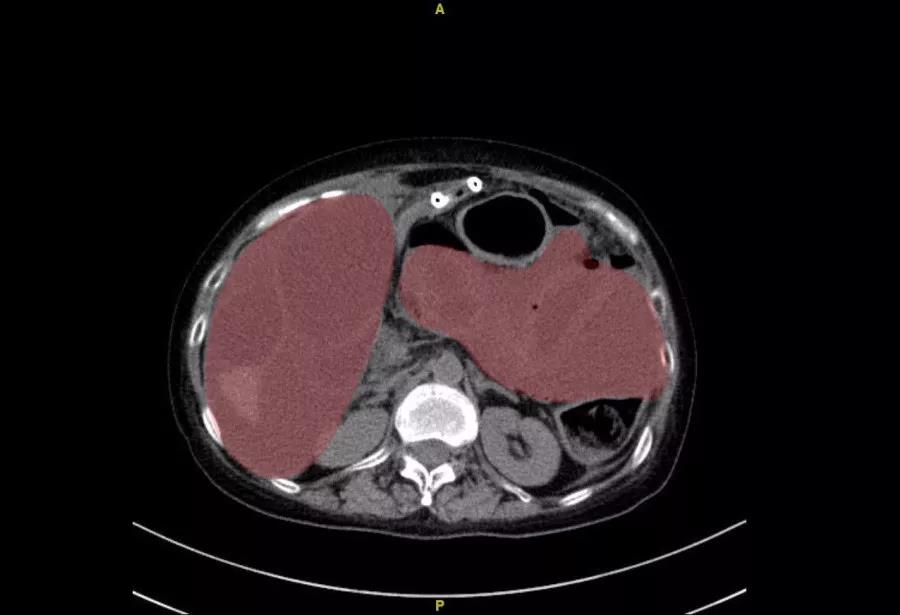

患者腹腔增强CT,红色部分均为粪液

就在医学专家们会诊的同时,王女士再次陷入昏迷中,此时已经是深夜11点,时间就是生命,各位专家毫不犹豫,直接冲到手术室,备战手术,要为患者打开了一条生命的通道。在麻醉医师的支持下,罗成华主任、苗成利副主任医师主刀进行手术。即便之前已经做出了精准的预判,也预知了手术的难度,但当打开患者腹腔的那一瞬,还是让手术台上的医护人员大吃一惊,现实原比预先设想的更加糟糕。王女士的腹腔内不仅有近千毫升的粪液,还有数个苗勒氏管肉瘤的转移瘤侵犯了多个器官,以至于全结肠完全坏死。这种情况下,一场手术下来,要处理的问题远超于一场普通的手术,这是一场硬仗,而且是必须打赢的战斗!